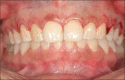

The containment of the elevator muscle of the upper lip and wing of nose was used for the treatment of patients with gummy smile. This technique had corrected esthetic alterations of smile, reducing the upper lip elevation, which results in a smaller gingival display. An upper lip lengthening as well as a reduction in the upper lip shortening when the patient smiled could be observed. The high smile line was corrected without compromising the labial harmony. This study presents an innovative and effective therapeutic option to obtain a natural and harmonious smile. The patient expressed a high degree of satisfaction.